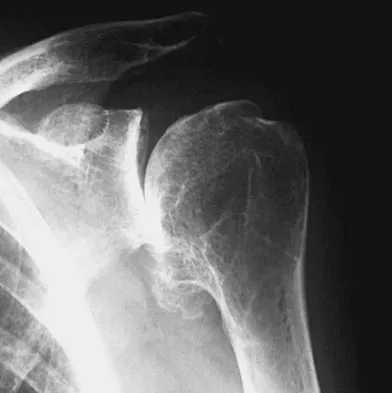

Figures 10a and 10b show the radiographs of a 47-year-old man who reports pain in both shoulders. He has a history of leukemia that was treated with chemotherapy and high-dose cortisone. What is the most reliable treatment option for pain relief in this patient?

Explanation

The radiographs reveal osteonecrosis with collapse. The most reliable and durable treatment for osteonecrosis of the humeral head remains prosthetic shoulder arthroplasty. Osteonecrosis of the humeral head may be seen after the use of steroids, and there is an increasing demand for shoulder arthroplasty in young people because of the use of high-dose steroids in chemotherapy regimes for the treatment of malignant tumors. The indications for most shoulder arthrodeses today include posttraumatic brachial plexus injury, paralytic disorders in infancy, insufficiency of the deltoid muscle and rotator cuff, chronic infection, failed revision arthroplasty, severe refractory instability, and bone deficiency following resection of a tumor in the proximal aspect of the humerus. Clearly, the role of arthroscopy and related minimally invasive techniques in the treatment of humeral head osteonecrosis remains unknown. Hasan SS, Romeo AA: Nontraumatic osteonecrosis of the humeral head. J Shoulder Elbow Surg 2002;11:281-298. Hattrup SJ: Indications, technique, and results of shoulder arthroplasty in osteonecrosis. Orthop Clin North Am 1998;29:445-451.